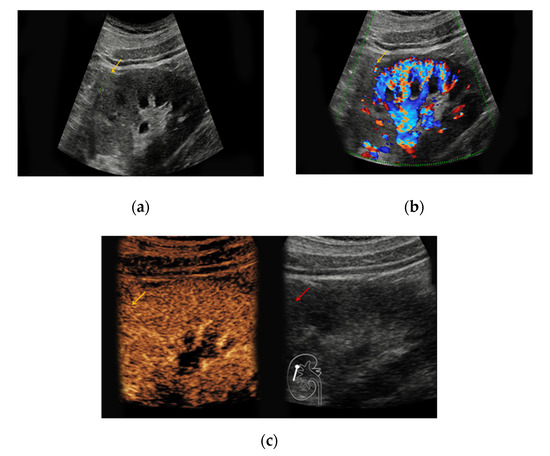

Figure 1. Renal oncocytoma in the right kidney with a diameter of 1.2 cm. (a) In native B-mode, the lesion presents as slightly hyperechoic (yellow arrow); (b) the lesion shows discrete vascularization in Doppler mode. (c) Upon intravenous application of SonoVue®, the lesion shows no signs of hyperenhancement.

Supplementary Table S1 illustrates the varying sonomorphological characteristics of renal oncocytomas and angiomyolipomas. No significant statistical differences between the sonomorphological features of benign vs. malignant lesions could be detected (Table 1). In native B-mode, oncocytomas presented as hypoechoic in seven cases (64%), as hyperechoic in one case (9%), and as isoechoic in one case (9%). Two lesions could not be detected in native B-mode and Doppler mode but demarcated upon intravenous application of SonoVue® showing rapid contrast-enhancement (18%). Only three lesions showed slight hypervascularization in Doppler mode (27%). In all patients with histopathologically confirmed oncocytoma, early contrast-enhancement upon application of SonoVue® could be detected (100%) (Figure 1). Seven of those lesions also showed venous wash-out (64%).